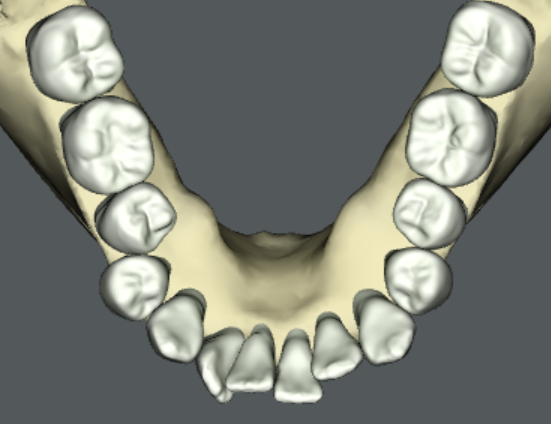

旭川公園通り矯正歯科では、問題点を解決するバーチャルセットアップを作成します。バーチャルセットアップとは、歯を動かす治療計画を三次元の仮想患者モデル上に再現したものです。個々の歯がどの経路を通ってどのくらい動くのかを視覚的に理解することができます。外科的矯正治療が必要な場合は、バーチャルオステオトミー(仮想患者モデル上での骨の移動)を行うこともあります。

当院で提供しうる治療方法と目標の全てを患者さんにご提示して、それぞれの利点と欠点、リスクとベネフィットをご説明します。患者さんには、バーチャルセットアップで可視化された治療目標を見ていただきながら、どの治療方法で矯正治療を開始するか共通認識のもとで決定していただきます。これが旭川公園通り矯正歯科で実施している「インフォームドチョイス」です。